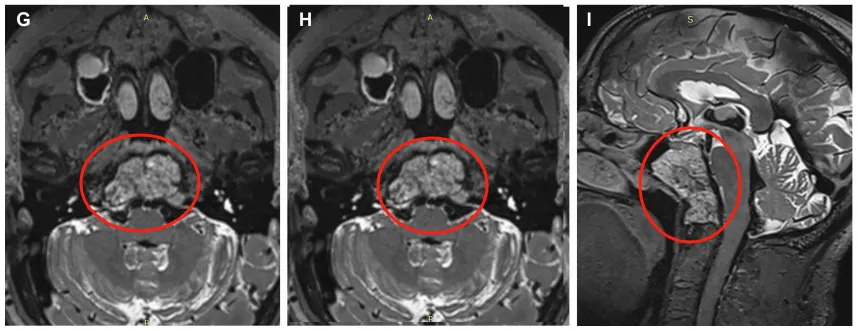

▼术前MRI显示一个大的斜坡脊索瘤延伸到蝶窦,寰枢椎、岩尖、下斜坡和右枕髁。